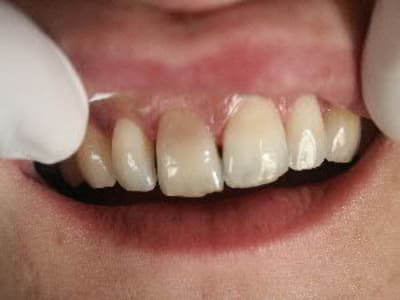

Quelles sont les chances de succès d'un blanchiment interne sur cette coloration due à un choc (pas de réaction aux stimuli thermiques,asymptomatique,disparition totale de la chambre et du canal)

facettes 11 et 21...

blanchiment externe au fauteuil(bluecool ou autre) ou ambulatoire a concentration elevee

je déconseille absolument le blanchiment dans un cas pareil

d'abord en externe car l'intensité de l'imprégnation colorée par voie interne me paraît condamner à l'échec

-pour les habitués des facettes : une facette permettra t'elle de faire disparaitre totalement la coloration et de rendre les caractérisations marquées de la dent adjacente,faut il tailler plus profondement que pour une facette classique,quelle type de céramique utiliser